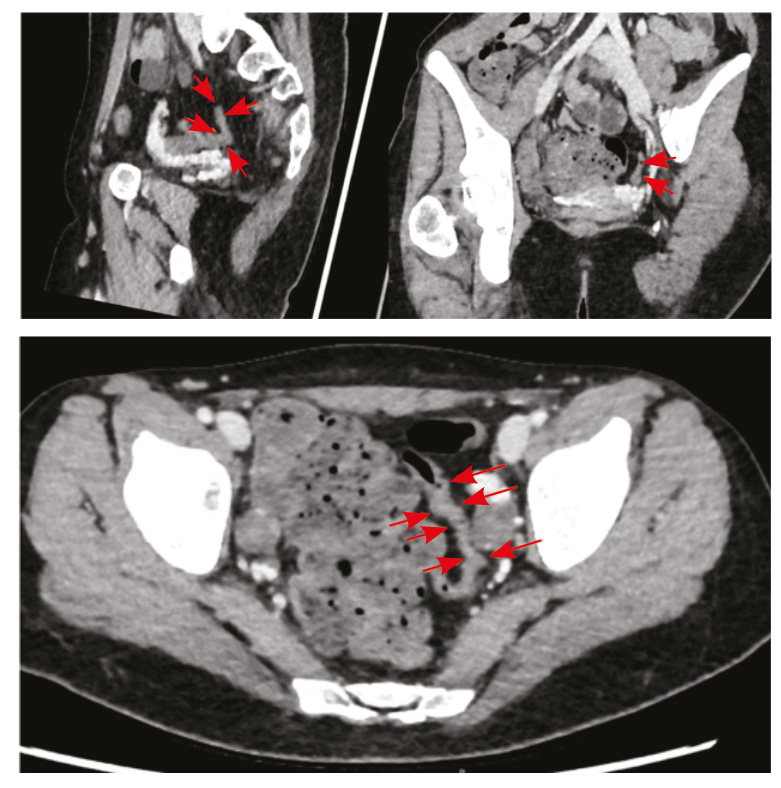

По результатам КТ органов брюшной полости с контрастным усилением, КТ- энтерографии определено утолщение стенки сигмовидной кишки до 5 мм на протяжении 60 мм, стенка без повышенного контрастирования (толщина стенки в остальных отделах не превышала нормы (2–3 мм), петли тонкого и отделы толстого кишечника расположены типично, стенки их с равномерным накоплением контрастного вещества, без достоверного наличия дополнительных образований, рельеф слизистой без отека, параколическая клетчатка не уплотнена, брыжеечные лимфатические узлы не увеличены. Заключение: КТ-признаки утолщения стенок сигмовидной кишки (поствоспалительные, постколитические изменения?), узелковая гиперплазия левого надпочечника (рис. 2).

Рис. 2. Компьютерная томографическая энтерография (30.03.2022). Стрелками указан измененный участок сигмовидной кишки: стенка утолщена до 5 мм на протяжении 60 мм, без повышенного контрастирования

Ультразвуковая доплерография сосудов брюшной полости: незначимый стеноз нижней брыжеечной артерии до 50%.

В основе поражения кишечника при АТ лежит хроническая мезентериальная ишемия, которая вызывает обратимые или необратимые повреждения. К обратимым относят колопатию, проявляющуюся отеком и субэпителиальными кровоизлияниями, и колит – как следующую стадию патологического процесса с изъязвлениями слизистой оболочки [26]. У нашей пациентки наблюдался гемодинамически незначимый стеноз нижней брыжеечной артерии (50%), поэтому поражение слизистой оболочки толстой кишки носило обратимый характер.

У описанной нами пациентки имелись характерные вышеуказанные признаки – метеоризм, неустойчивый стул, значительная потеря массы тела (13 кг) и обратимая колопатия. При этом изменения стенки кишки локализовались преимущественно в сигмовидной кишке (утолщение стенки сигмовидной кишки на протяжении 60 мм по данным КТ-энтерографии). Сегментарность в данном случае в сочетании со стенозом нижней брыжеечной артерии говорит об ишемическом характере поражения. По данным литературы, поражение брыжеечной артерии при АТ происходит в 11–28% случаев [34] и проявляется дискомфортом в животе, вздутием [35].